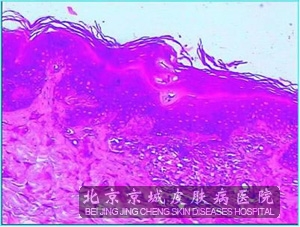

北京京城皮肤医院指出:原发性淀粉样变的组织病理为苔藓样淀粉样变的表皮棘层肥厚和角化过度,斑状淀粉样变的色素失禁较好,淀粉样蛋白沉积比苔藓样淀粉样变少,染色淀粉样蛋白呈均质性,轻度嗜酸性团块,有裂隙,固定和脱水过程中,淀粉样蛋白收缩引起的。